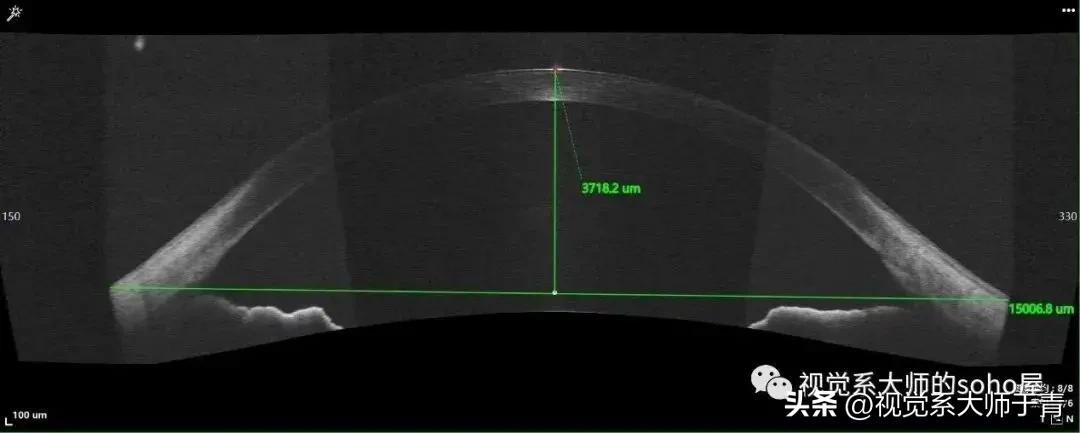

这个患者15mm弦长下的角膜矢高3718μm(拍摄设备:视微影像OCT VGS,下同)

巩膜镜的验配主要依据矢高的概念进行,角膜k值在巩膜镜验配过程中反而不是那么重要。可以先行测量或者计算巩膜镜同等弦长下的角膜矢高。而镜片的矢高会受直径、弧度、角膜非球面性以及巩膜前表面形状的影响。由于在临床不容易测得巩膜前表面形状,所以无法计算实际的矢深,除非使用像OCT这类测量范围更广的设备。